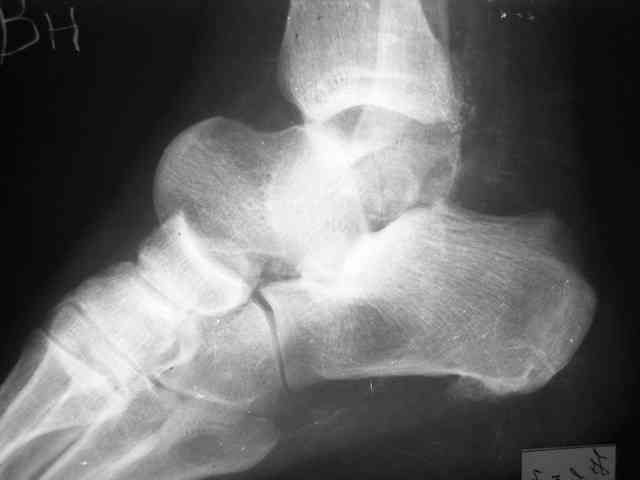

Уважаемый Александр! Как обещал представляю Р-граммы и операционные фото.

Мнение по поводу тарана? АН есть?

> Мнение по поводу тарана? АН есть?

Типичная картина некроза.

Если очаг инфекции - не весь блок, и удастся инфицированную часть хорошо убрать, то будут неплохие шансы на васкуляризацю тарана с двух сторон. Послеоперационные рентгенограммы, конечно, будет интересно посмотреть. Они, правда, вряд ли прогноз надежно отразят.